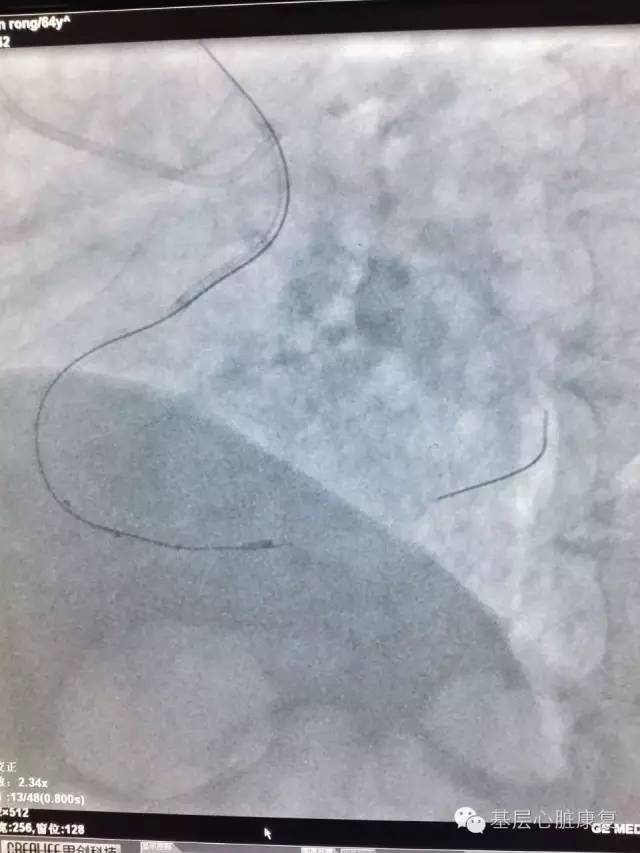

汗水湿透了手术衣而浑然不知,厚重的铅衣未能压垮必胜的信念。忘记了时间,忘记了疲劳,忘记了家里的老小。面对复杂的器械和病变,脑子时刻清晰不能有一丝混乱,心中的执着不能有一点懈怠。眼睛紧盯屏幕捕捉每一刻的影像,手中的钢丝在IVUS指导下探寻着通往光明的每一丝线索, 直至导丝穿入真腔并沿真腔前进,到达远端血管病变。